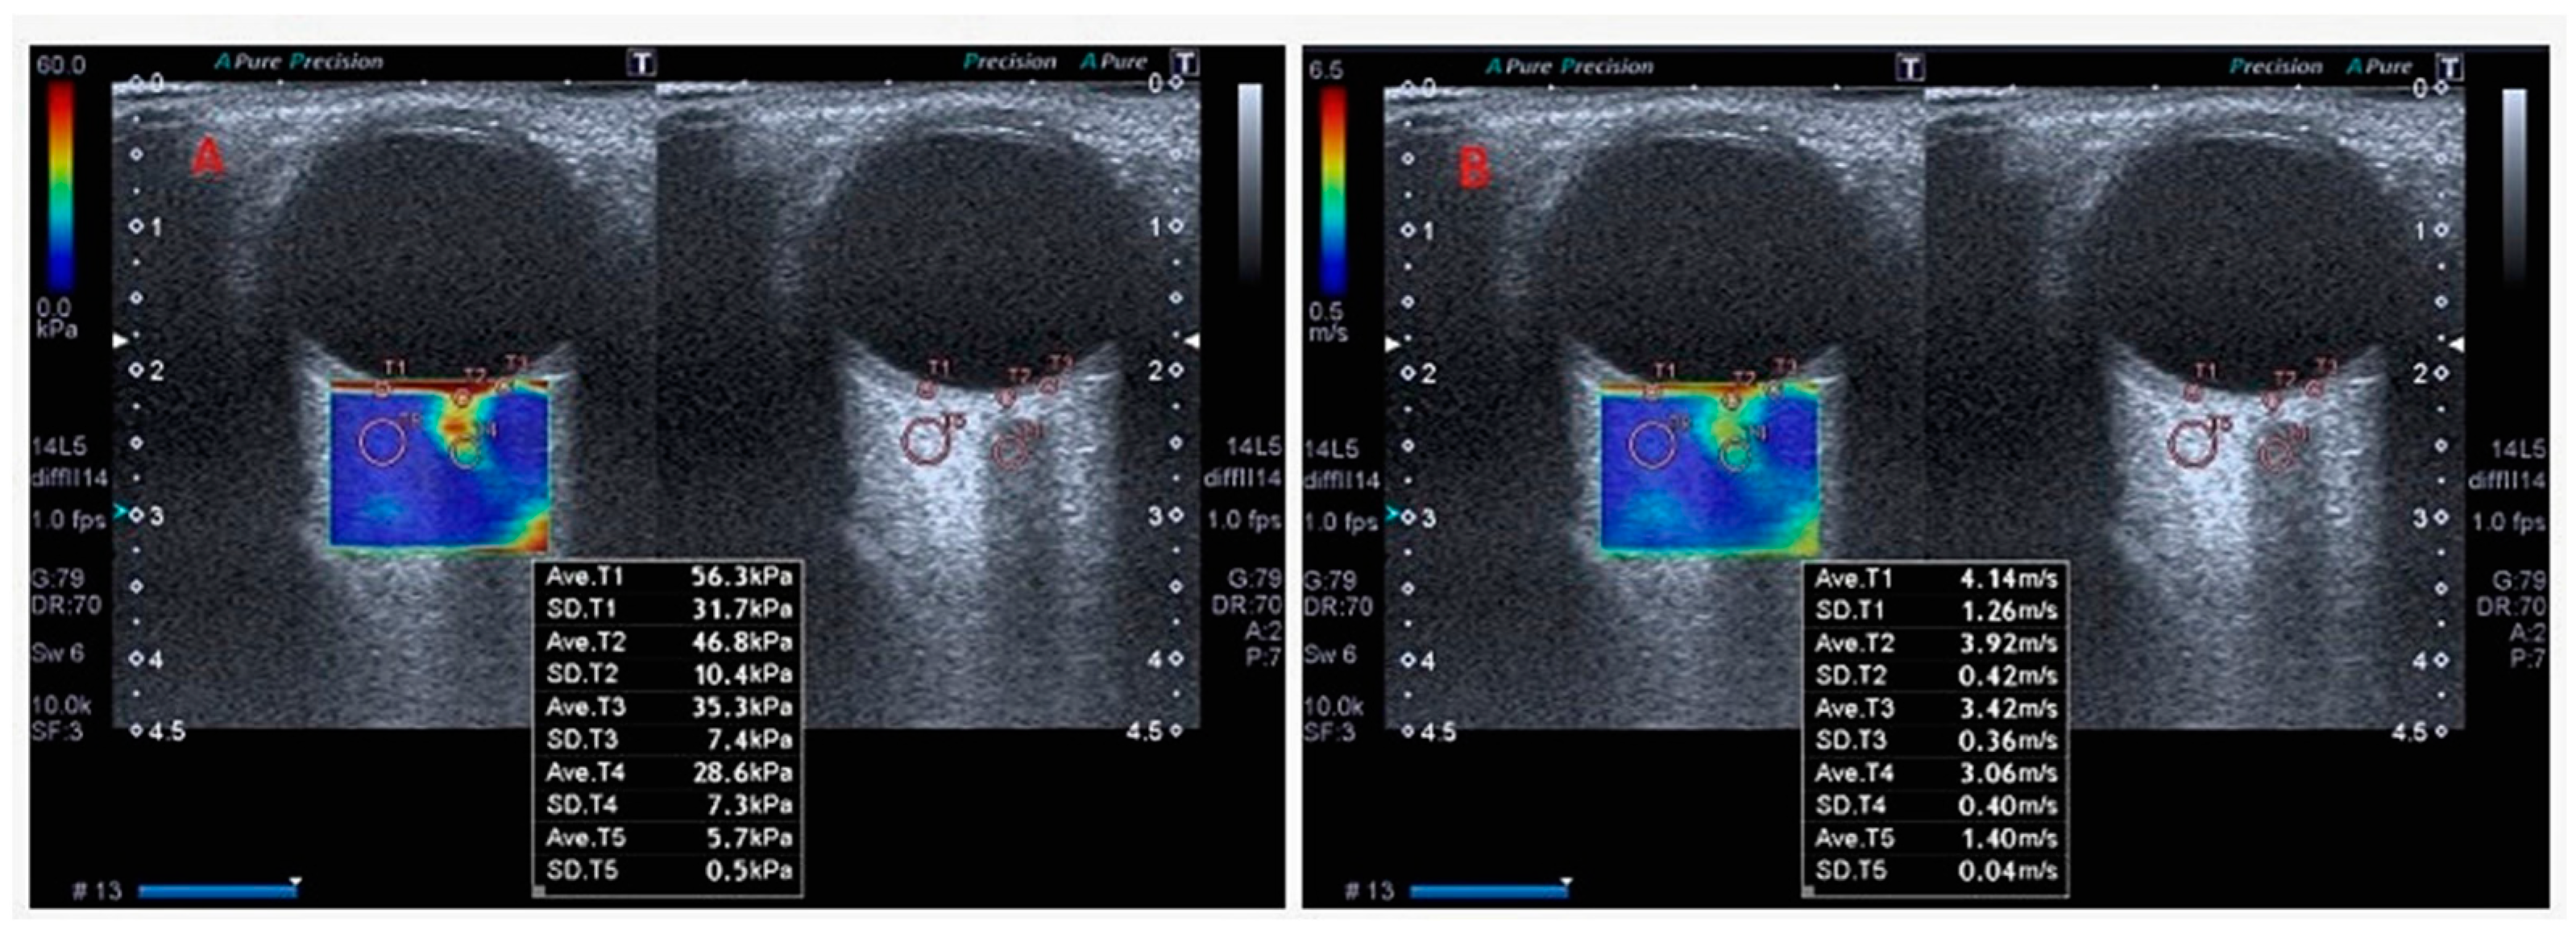

2.3. Orbital SWE Examination